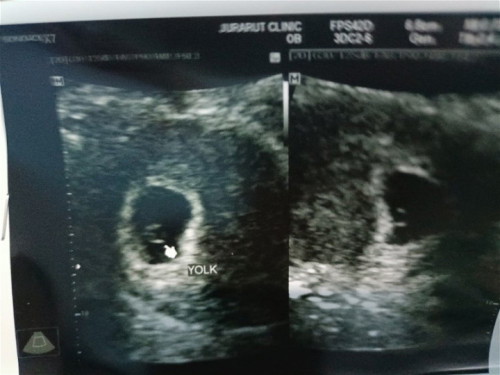

วันนี้ไปฝากท้องมาอายุครรภ์6week6day เจอถุงตั้งครรภ์เจอตัวอ่อน แต่ยังไม่ได้ยินเสียงหัวใจน้อง หมอบอกว่าน้องยังตัวเล็กมากๆๆ หมอนัดอีกที2อาทิตย์ แม่ๆบ้านอื่นได้ยินเสียงหัวใจน้องตอนกี่วีคคะ บ้านนี้ยังกังวลอยู่เลยคะ อยากได้ยินเสียงหัวใจน้องแล้ว